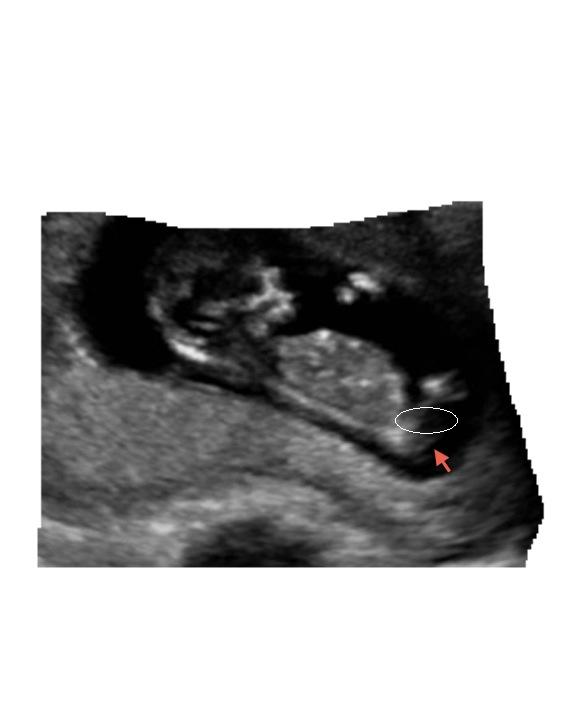

Is this the nub?Attachment 6637

Im thinking it is here, can only just see something angled up here so id guess boy